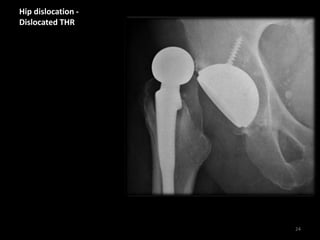

Hip dislocation

• (dislocation of the femoral

head from the acetabulum)

is most frequent following

total hip replacement

(THR). Dislocation is usually

in a posterior direction

which clinically leads to leg

shortening, with flexion and

internal rotation at the hip

(note - hip fractures usually

cause external rotation).

• may be accompanied by

fracture of the

acetabulum, or

significant soft tissue

injuries not visible with

X-ray.

Hip dislocation -

Dislocated THR

Patient with Total Hip

Replacement (THR)

The ball of the femoral

component is displaced

from the cup of the

acetabular component